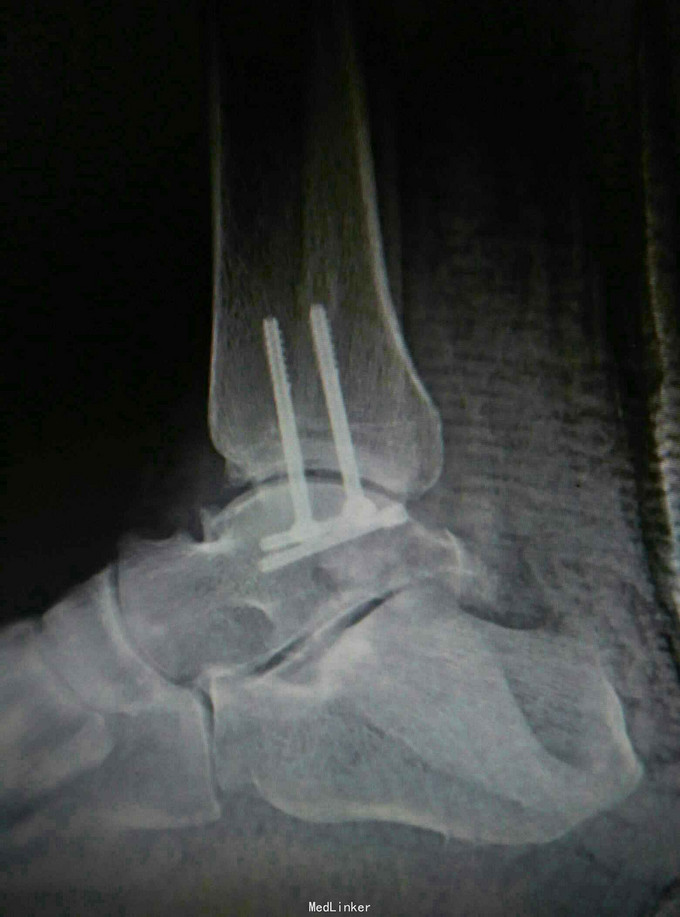

患者,男,45岁,车祸伤致右踝部肿痛,活动受限2小时入院

入院查体见局部肿胀,予完善影像学检查,

诊断是右距骨粉碎性骨折。给予行内踝截骨显露骨折端进行复位,采用Herbert钉进行固定。

术后复查X线片提示骨折端完全复位,内固定固定在位良好。 讨论:距骨骨折的主要并发症是坏死,骨不愈合等,但近年来随着对其认识的不断明确,治疗比较规范,积极的进行切开复位,并行坚强固定,近年的研究报告提示距骨的坏死率是不断在下降的,当然前提是进行有效复位并坚强固定。